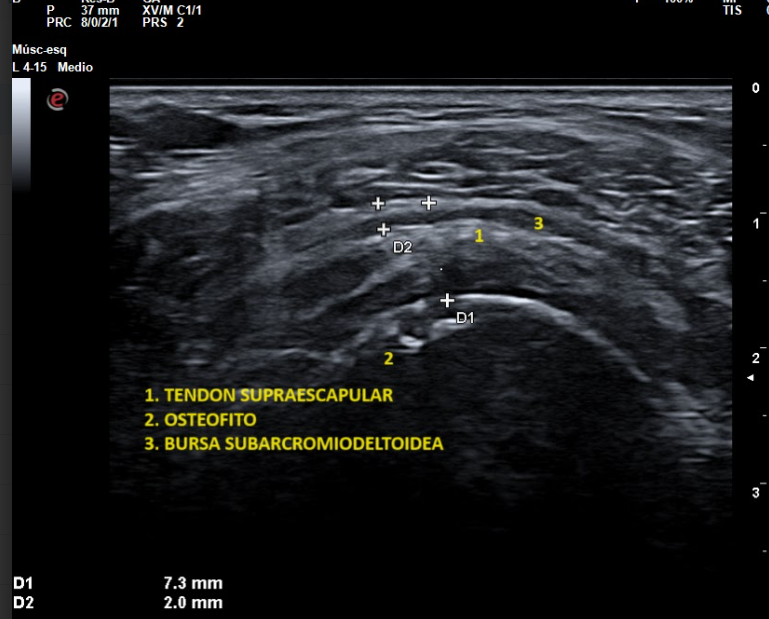

La ecografía musculoesquelética en Madrid es una técnica de diagnóstico por imagen de alta precisión que permite valorar en tiempo real músculos, tendones, ligamentos y articulaciones. En nuestra clínica ofrecemos este servicio con especialistas en dolor y traumatología, utilizando equipos ecográficos de última generación.

Es un estudio no invasivo que utiliza ondas de ultrasonido para obtener imágenes detalladas de las estructuras del aparato locomotor. A diferencia de otras pruebas, como la resonancia magnética, la ecografía permite una exploración dinámica, observando los movimientos de músculos y tendones durante la exploración.

La ecografía articular y muscular en Madrid es útil para el diagnóstico de múltiples patologías:

• Lesiones musculares (roturas, desgarros, contracturas).

• Lesiones tendinosas (tendinitis, roturas parciales).

• Bursitis y sinovitis.

• Patologías articulares (artrosis, artritis).

Además, la ecografía cervical, de rodilla, pie o cadera permite estudiar zonas específicas y localizar con exactitud el origen del dolor.